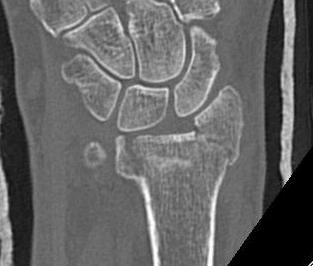

Distal Radius Fracture DRUJ incongruentDRUJ FractureDRUJ Fracture CT

Sigmoid notch disruption and DRUJ instability